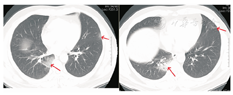

患者男,47岁,黑龙江省哈尔滨市人。因"发热5 d"于2020年1月21日收入我院发热留观病房。既往健康,否认慢性病史及传染病史。患者为火车司机,往返于哈尔滨——武汉区间。发病前两周曾两次随车到达武汉,并在武汉火车站站台逗留。2020年1月16日开始出现发热,体温在37.5~39 ℃,伴畏寒,无寒战。无咳嗽及咯痰,无喘息及呼吸困难。入院前1 d曾有轻微腹泻症状,排稀便两次,未见脓血。入院后查体:一般状态尚可,呼吸平稳,体温38.2 ℃,脉搏108次/min,呼吸16次/min,血压140/95 mmHg(1 mmHg=0.133 kPa)。球结膜轻度充血,双肺听诊呼吸音清,未闻及干湿啰音。入院当日在我院发热门诊行血常规检查:白细胞(WBC)6.14×109/L,中性粒细胞占比0.560,淋巴细胞占比0.337,淋巴细胞绝对计数2.07×109/L,单核细胞占比0.103,红细胞及血小板计数正常。胸部CT:左肺及右肺上下叶可见斑片影,边界模糊。影像学诊断:左肺及右肺上下叶炎性改变(图1)。入院当日市疾控中心行咽拭子2019-nCoV核酸检测阴性,其他相关检查结果:C-反应蛋白16.8 mg/L(参考值0~8 mg/L),红细胞沉降率38.00 mm/1 h(参考值0~15 mm/1 h),降钙素原0.10 ng/mL(参考值0~0.046 ng/mL),肌红蛋白203 ng/mL(参考值0~154.9 ng/mL),肌酸激酶1 149.60 U/L(参考值38~174 U/L),G-脂多糖、肝肾功能、凝血功能正常。相关病原学检查:甲型流感病毒、乙型流感病毒、副流感病毒-2型、嗜肺军团菌、肺炎支原体、肺炎衣原体、Q热立克次体、腺病毒、呼吸道合胞病毒、风疹病毒、单纯疱疹病毒、巨细胞病毒、弓形虫IgM抗体均阴性。EBV DNA定量<5.0×102拷贝/mL。入院当日开始静脉点滴盐酸莫西沙星氯化钠注射液(0.4 g/d),口服磷酸奥司他韦胶囊(75 mg/次,2次/d),补液对症治疗。1月23日,患者仍有间断高热,体温可达40 ℃。偶有轻微干咳,无痰。市疾控中心第2次咽拭子2019-nCoV核酸检测仍为阴性,我院复查血常规:WBC 4.89×109/L,中性粒细胞占比0.583,淋巴细胞占比0.319,淋巴细胞绝对计数1.56×109/L,单核细胞占比0.098。胸部CT:双肺可见斑片影及磨玻璃影,边界模糊。影像学诊断:双肺炎性改变(图2)。咽拭子细菌培养、血细菌+真菌培养未检出病原体。继续给予上述药物治疗,同时行物理降温,未应用退热药物。因两次2019-nCoV核酸检测阴性,建议患者回家中自行隔离治疗。1月24日患者仍有发热,咳嗽频繁,咯白痰,且患者配偶亦出现发热症状,即到我院急诊内科留观隔离,继续予盐酸莫西沙星氯化钠注射液静脉点滴、口服磷酸奥司他韦胶囊(两种药物剂量同上)。1月26日患者仍发热,体温最高达38.5 ℃,自觉胸闷、呼吸急促,查动脉血气分析:PaO2/FiO2:342 mmHg。血常规:WBC 4.37×109/L,中性粒细胞占比0.687,淋巴细胞占比0.197,淋巴细胞绝对计数0.86×109/L,单核细胞占比0.115。胸部CT:双肺可见淡片影,磨玻璃影,范围较前扩大,边界不清。影像学诊断:双肺炎症(图3)。1月27日我院组织院内专家会诊,认为该患者虽然两次2019-nCoV核酸检测阴性,但结合流行病学史及临床表现(高热,淋巴细胞计数进行性减少、肺部间质性病变且进行性加重),不能排除2019-nCoV感染,申请市疾控中心行第3次咽拭子2019-nCoV核酸检测,结果仍为阴性。患者仍维持原治疗方案治疗。1月28日患者体温趋于正常,自行离院,在家中继续隔离治疗。每3日对患者进行电话随访,患者未再出现发热,咳嗽、咯痰明显缓解,未出现呼吸困难。因疫情期间特殊情况,未到我院进行相关复查。